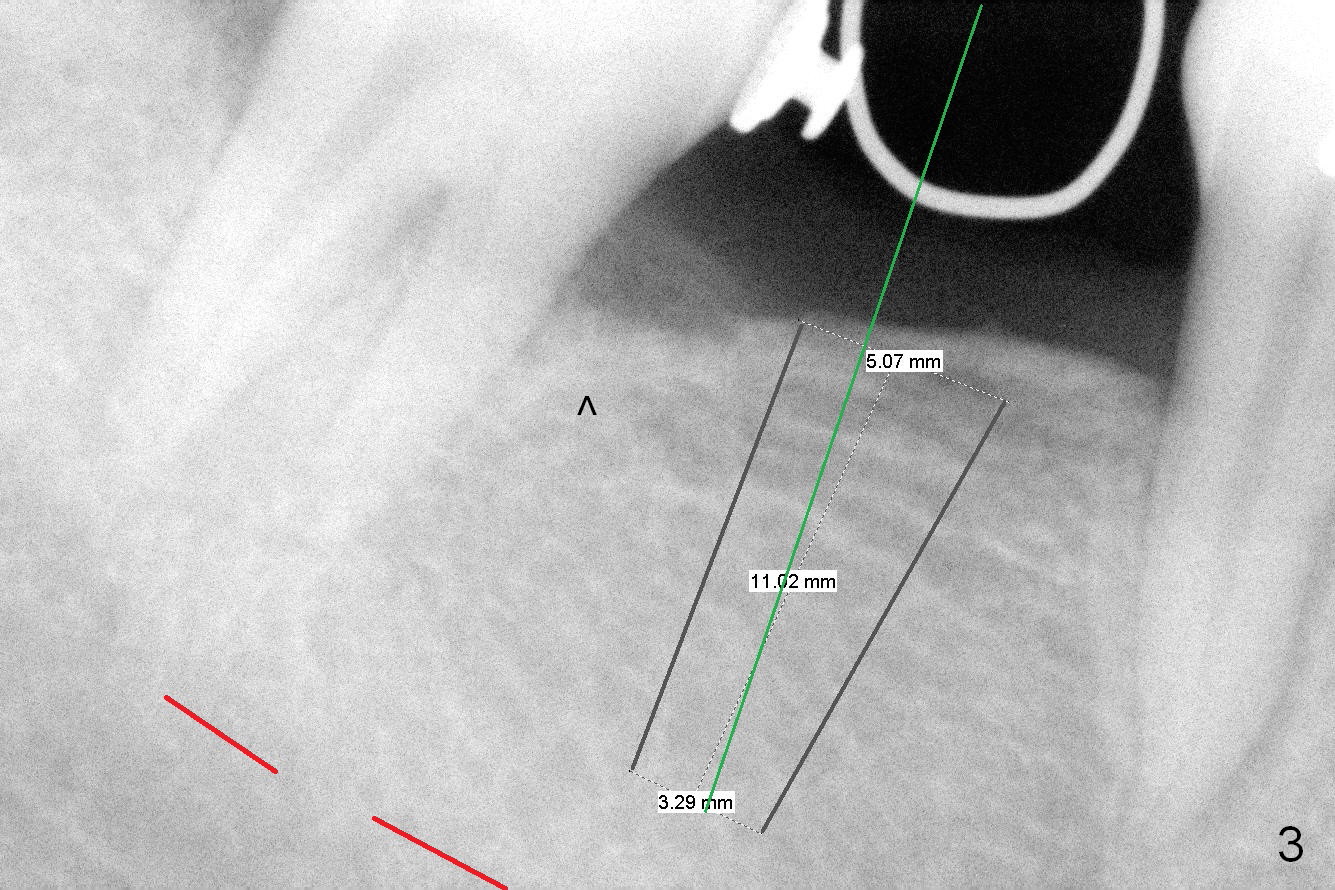

The ridge is found to be fairly narrow after incision. Bone density is determined to be high using #15 blade. A 1.6 mm pilot drill is used to initiate osteotomy (Fig.4). The latter is moved mesially. By the time 3.3 mm Magic Drill is in place, the osteotomy is in the better position mesiodistally (Fig.5). The same is a 4x11 mm IBS implant (Fig.6, >55 Ncm). The lingual button in the mesial of #31 is then removed, because it appears to interfere with placement of a 4.5x4(2) abutment. The position of #31 is maintained by open coil spring.